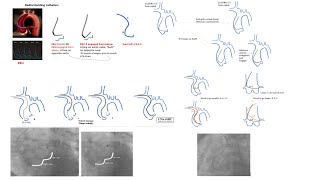

Left+right coronary engagement for general fellows: step-by-step tips, diagrams, caveats (5 for RCA)

Left EBU/CLS guides manipulations, radial and femoral +Ikari L +Key tips in left coronary engagement

Left coronary engagement (radial focus): detailed steps, diagrams, tips, and case videos-Elias Hanna